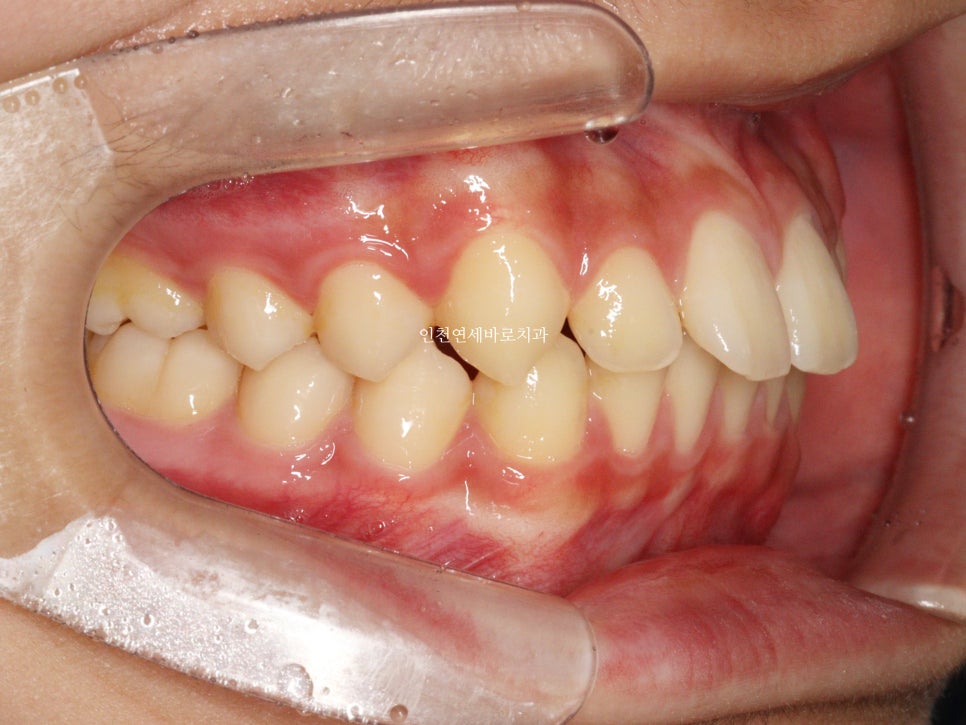

치료 전과 후 입니다.

앞니가 후방이동 한것이 확인됩니다.

우리는 부분교정을 한것이 아니라 간단한 전체교정을 한것입니다.

치아가 들어가보입니다.

앞니만 철사를 붙여서는 얻기 어려운 결과라고 생각합니다.